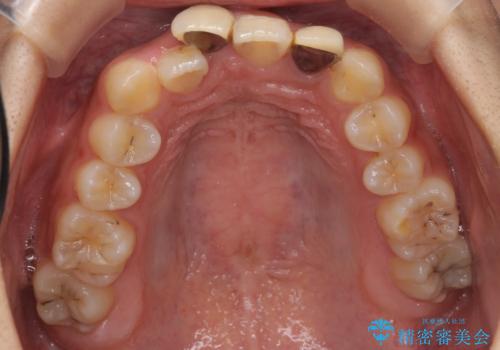

前歯のがたつき 保険治療の前歯の被せ物もやりかえたい

- 前歯のがたつきを主訴に来院。

保険治療の被せ物が前歯に2本あり、矯正治療で移動後にセラミックでやり替えを行っています。

右上のかみ合わせがずれていたため、インプラント矯正を行い、奥歯を後ろに下げて治療しています。